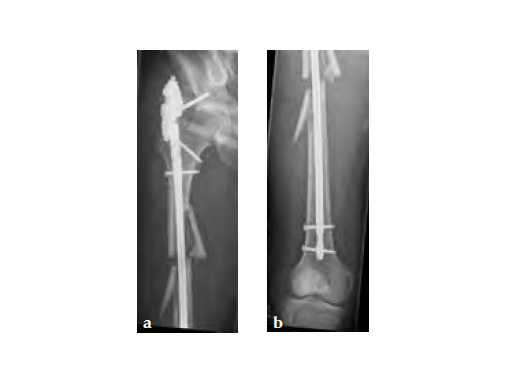

Three weeks prior to her last admission, she complains of recurrent right thigh pain for which epidural analgesics were administered for presumed radiculopathy, however preliminary x-rays and even MRI of the thigh were also taken in view of her primary complaint regarding her right thigh. These investigations did not indicate the possibility of impending bisphosphonate related femur fracture. It is clear from the radiographs that she has an obvious anterolateral bow of her femur and a thickened lateral cortex in the lateral midshaft cortical bone, which may indicate a stress fracture (see Fig 3a-b).

No edema indicated a stress fracture (see Fig 4a-b).

Based on the negative MRI thigh and positive MRI lumbar spine of multiple levels of spinal stenosis, the patient underwent epidural analgesic injection. Patient sustained right femur midshaft periprosthetic fracture the next day after her epidural injection with no trauma.

Notice the fracture decrease the emphasis on the anterolateral bow of the femur (See Fig 5a-b).